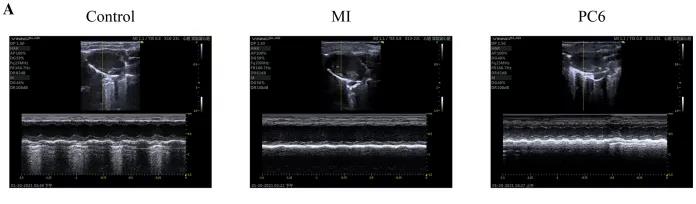

為了探討針刺PC6穴對心肌損傷的影響,作者首先評估了心功能和梗死面積。超聲心動(dòng)圖結果顯示MI組的EF(ejection fraction)和FS(fractional shortening)均較對照組明顯降低。PC6穴位治療后,EF和FS均增加。針刺治療5天后, 采用TTC染色檢測梗死面積。結果顯示,針刺治療顯著(zhù)減小心肌損傷的大小。采用ELISA法測定反映急性心肌損傷的心肌特異性血清酶,包括心肌肌鈣蛋白T (cTnT)和心肌肌鈣蛋白I (cTnI)的水平。結果表明,心肌梗死術(shù)后cTnT和cTnI水平升高,針刺可顯著(zhù)降低血清酶水平。